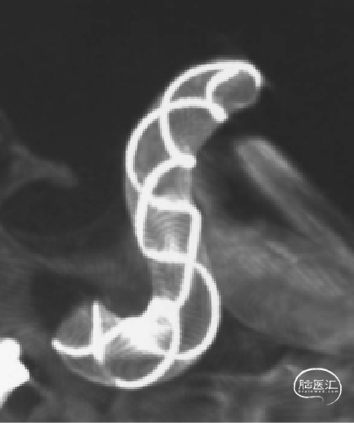

TB Plus 4/35

3、释放TB Plus过程中,头端铆钉效果满意,释放过程顺滑。

4、通过微导丝按摩,可以使TB Plus贴壁效果更加。

6、Tubridge Plus材料改进后通体显影,可以更好观察支架的贴壁性及术中打开情况,提高释放安全性。